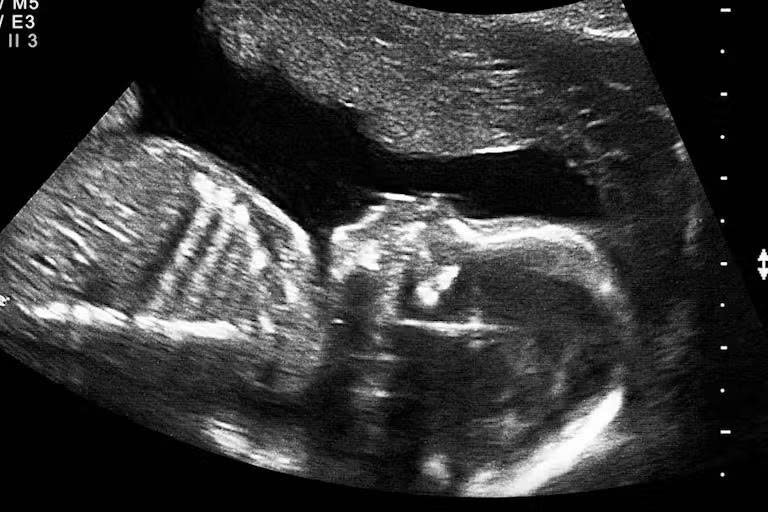

As the nurse was performing the ultrasound, I watched her, and she was looking at my baby on the monitor. And I asked her, I said, “Can I see my baby?” And she took the monitor, literally, with her hands, and turned it away from me.

Another woman said, “As I was watching the monitor, the nurse and the doctor asked me not to watch. They turned the monitor away.”

Another woman described how the abortion worker got angry when she looked at the ultrasound screen. “And I turned to look at the screen and thought, ‘that looks like a baby,’” she said. “Well, she got very upset and yelled at me, and said, ‘turn around, don’t you dare look at that!’”

And they had the screen turned away from me. And I asked to see it. And she said, “I don’t think it’s a good idea.”

I told her, “no, I really wanted to see it before I went through with it.”

So, she ran the probe across my stomach, turned the screen toward me, and showed me a dot on the screen. I thought, “that’s it? Well, I can do this.”…

I bought the lie. I now know, she didn’t show me my baby. She just showed me a dot on the screen so that I would go through with the abortion.

The abortionist knows that if the mother knew there was a heartbeat or saw the fetus (baby) on the ultrasound, she would probably change her mind about the abortion. When an ultrasound was performed at the abortion clinic, the screen was turned away from the mother and the sound was turned off so the mother could not hear or see it.